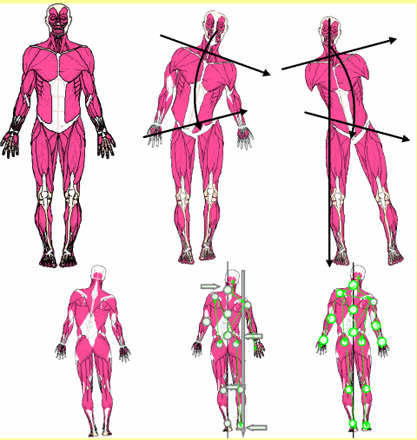

Dieses zeigt die Körper-Statik, respektive die Fehlstatik, immer über die gleiche vorgegebene Standhaltung unter Muskelspannung.

Alle Abweichungen erfolgen immer über die statische Körpermittellinie. Nur so werden

seitliche-, höhen-Abweichungen, Rotationen, Beinstellungen, mit Knieblockaden und Fehlbelastungen der Fuss-, Fuss-Stellungen im Zusammenhang ersichtlich und vermasst.

Diese Messdaten mit der ersichtlichen Körpersprache unterstützten die Suche nach den Ursachen, die so in eine Behandlung einfliessen. Das vereinfacht gezielte Anwendungen durchzuführen und den Verlauf reproduzierbar aufzuzeigen.

Mit Hilfe der Styfologie®-Ganz-Körper-Statik-Vermessung wird die Fehlstatik sicht-, mess- und behandelbar aufgezeigt. Zur Kontrolle kann in ca. 5 Minuten mit unserer Therapiematte aufgezeigt werden, ob es sich dabei nur um einen Beckentiefstand, oder um eine echte Beinverkürzung handelt.

Wie kann die Fehlstatik aus Körperteil-Aufnahmen Ursachen bezogen erkannt werden, die zu Knochen-, Gelenk-, Wirbelkörper-, Bandscheiben-Veränderungen führen?

Wie können so die verursachenden Muskel-Fehl-Spannungs-Linien erkannt werden?

Die Körper-Statik-Vermessung zeigt vieles einfach im Zusammenhang auf,

über die Statik (Fehl-Statik/ Hebelgesetz / Muskulatur / Sehnen, die über diese Ausweichhaltungen zu Beschwerden führen.

Die Körper-Statik-Vermessung zeigt vieles einfach im Zusammenhang auf.

Über Statik / Hebelgesetz / Muskulatur / Sehnen und Bänder / werden die Skelett Ausweichhaltungen präzise und reproduzierbar aufgezeigt, die über die Fehlbelastungen zu Beschwerden führen.

Würde die Ganz-Körper-Statik Vermessung eingesetzt, würde die Diagnose schnell und präzise die Ausweichhaltungen aufzeigen.

Würde die Ganz-Körper-Statik Vermessung bei den bildgebenden Verfahren eingesetzt, könnten Fehldiagnosen verhindert werden. Dies würde die Ursache der Skelett Ausweichhaltungen als Ursache der Muskelfehlspannungen aufzeigen.

Würde die Ganz-Körper-Statik Vermessung bei den bildgebenden Verfahren eingesetzt, könnten Fehldiagnosen verhindert und zudem viele Kosten gespart werden. Dies würde die Ursache der Skelett Ausweichhaltungen als Ursache der Muskelfehlspannungen aufzeigen.

Um auch die Ursache der Beschwerden aufzudecken, wird der Einbau der Ganzkörperstatik und des Hebelgesetzes benötigt, damit auch reproduzierbar die Gesamtkörperstatik berücksichtigt werden kann.

Die Vorteile

- vereinfacht die Diagnose:

alle Zusammenhänge in der Ganzkörperstatik werden aufgezeigt - reproduzierbare Messdaten:

Ausweichhaltungen und deren Verlauf werden einfach und klar dokumentiert - Behandlungs-Sicherheit:

Auslöser der Probleme werden durch die Ausweichhaltung sichtbar und können gezielt behandelt werden - verbesserte Qualität der Behandlung:

neben dem entstandenen Körperproblem (Auswirkung) wird auch die Ursache der Beschwerde über die Hebelgesetze erkannt. Durch die genaue Erkennung der Fehlspannungen können diese in einer Therapie mit einfliessen und so einen schnelleren Heilungserfolg ermöglichen - weniger Fehldiagnosen:

durch Mitberücksichtigung der Ganzkörperstatik und das Erkennen der Fehlstatik ist die genaue Bestimmung der Ursache möglich

Die Styfologie ® zeigt 9 Ausweichhaltungen zur rechten- und zur linken Seite auf. Diese ergeben 46 Kombinationsmöglichkeiten. Kann dies von blossem Auge festgestellt werden?